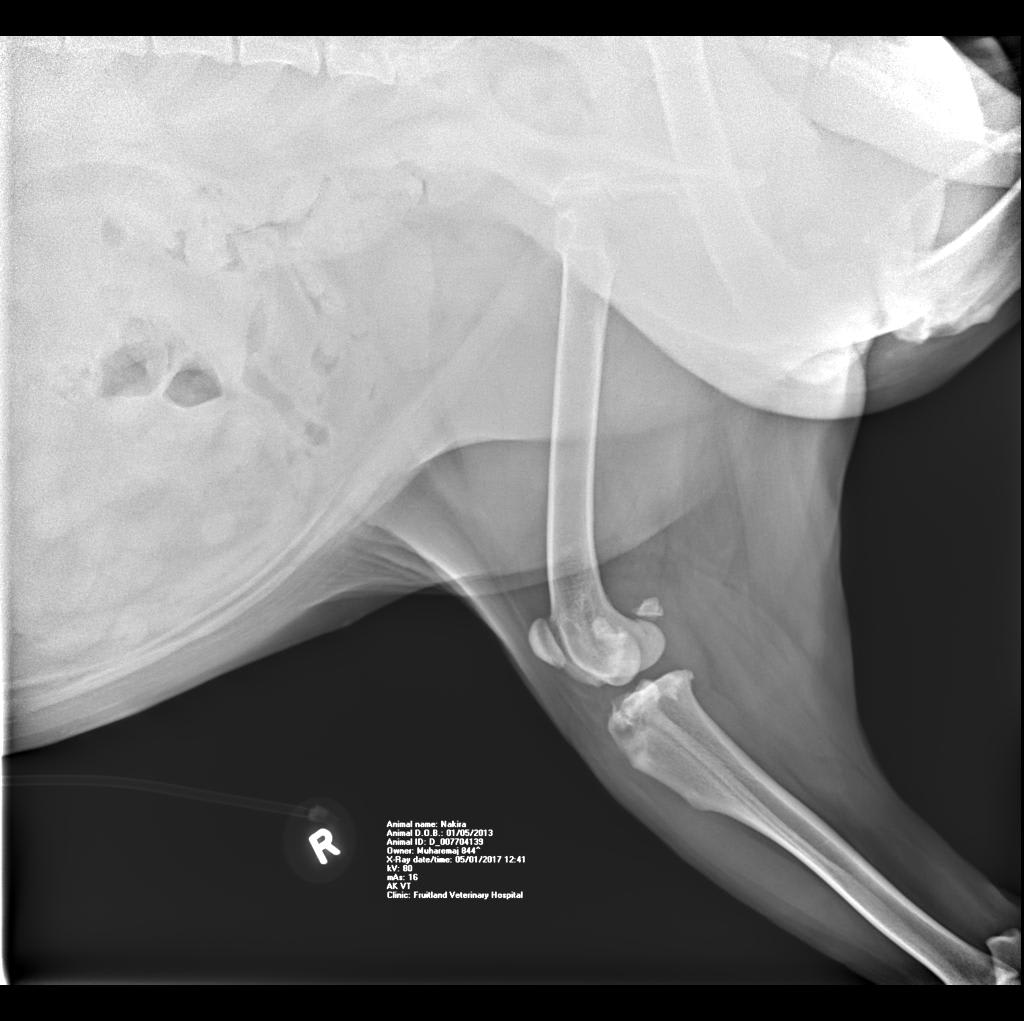

Hello there, I am looking for an expert HONEST opinion about my dog's knee condition...she is only 4 years old, and can barely walk (hind legs). A mastiff-bulldog mix, cca 130 lbs, ( on a special vet diet) spayed female. Motility problems started cca 18 months ago. I am attaching 3 x-rays. Is this a progressive illness and what is your recommendation (no surgeries). Thank you.